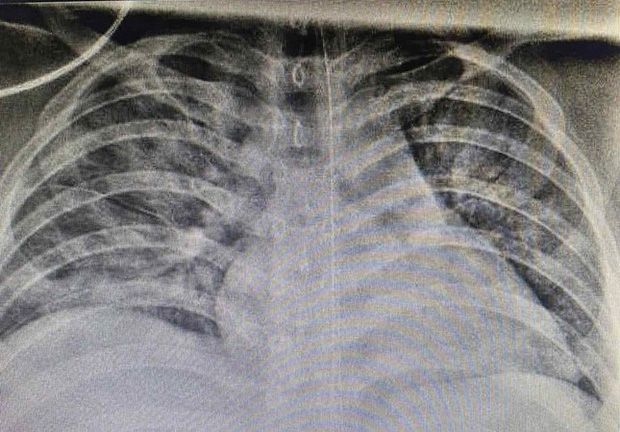

Tuy nhiên, tình trạng không cải thiện, hình ảnh X-quang phổi cho thấy, bệnh nhi bị tổn thương phổi nặng lan tỏa hai bên. Các bác sĩ đã tiến hành hội chẩn và nhận định trẻ có biểu hiện hội chứng suy hô hấp cấp tiến triển (ARDS) nên ê-kíp điều trị quyết định đặt nội khí quản cho thở máy.

Bệnh nhi đã được chăm sóc tích cực, điều chỉnh nước điện giải, toan kiềm, hạ sốt, dinh dưỡng, xoay trở chống loét. Sau gần 2 tuần thở máy với các thông số thích hợp, tình trạng cải thiện dần được cai máy thở, thở máy không xâm nhập, thở CPAP, thở oxy qua cannula rồi tự thở được với khí trời. Sau gần 1 tháng điều trị, bệnh nhân đã có xét nghiệm 3 lần âm tính với SARS-CoV-2, ngày 12/8 em được xuất viện về địa phương tiếp tục theo dõi y tế.